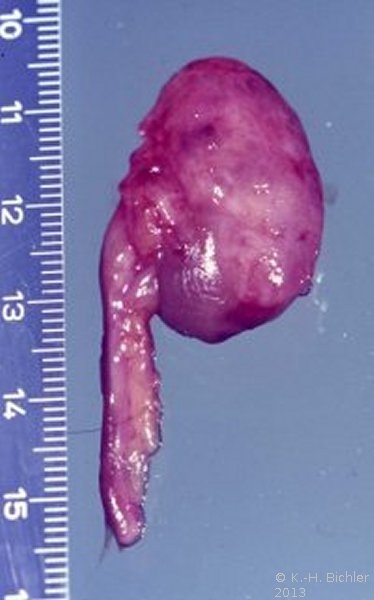

Es handelt sich pathologisch-anatomisch um eine kleine Niere mit einem Gewicht um 30g. Dabei sind die funktionellen Elemente (Renculi) numerisch reduziert auf 3 bis 5, normal 12 bis 14. Die Organanteile sind aber normal entwickelt (

Die echte Hypoplasie hat keine Komplikationen wie Hypertonie. Sie wird in der Regel zufällig entdeckt, im Gegensatz zur einseitigen pyelonephritischen Zwergniere mit Hypertonie. Die echte hypoplastische Niere ist selten. Zollinger fand unter 10.000 Obduktionen eine hypoplastische Niere. Die erworbenen Zwergnieren infolge entzündlicher oder vaskulärer Ursachen sind dagegen häufiger.